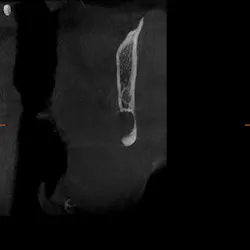

Upon examination, it was noted that a dark, radiolucent lesion was present on the lower right jaw, anterior to the angle of the mandible. The patient didn’t have any pain, symptoms, or knowledge of the lesion. It was not palpable. He reported that he had his third molars removed in his twenties with no complications.

Reflecting back on my amazing pathology education at Creighton University (thanks, Dr. Bob Achterberg!), I immediately tried to think of what my differentials could be. Full disclosure: I was worried that my patient’s jaw could break at any moment. I thought it was a residual cyst from third-molar removal.

The Stafne defect is code for a depression in the bone, a concavity, due to the submandibular gland. In addition, it can’t be qualified as a cyst because there is no epithelial lining or fluid content. It does usually occur more in men as well.1 There is no treatment necessary; it’s something we can just monitor.